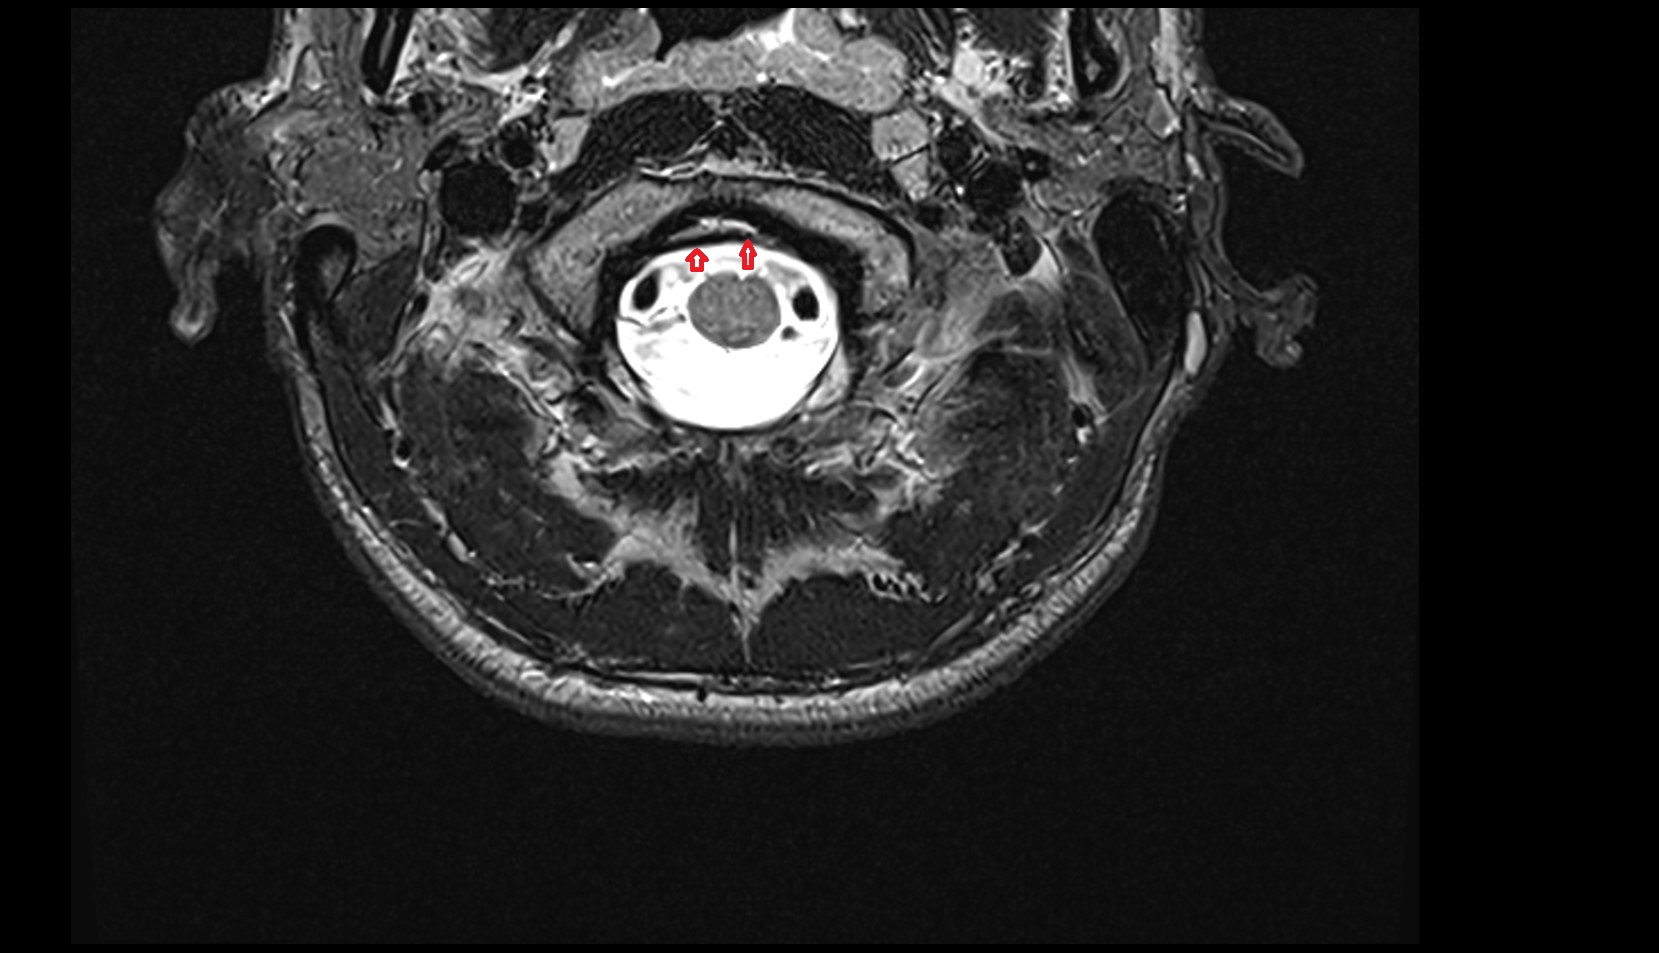

- Upper cervical spinal cord

- Spinal cord

- subarachnoid space of spinal cord